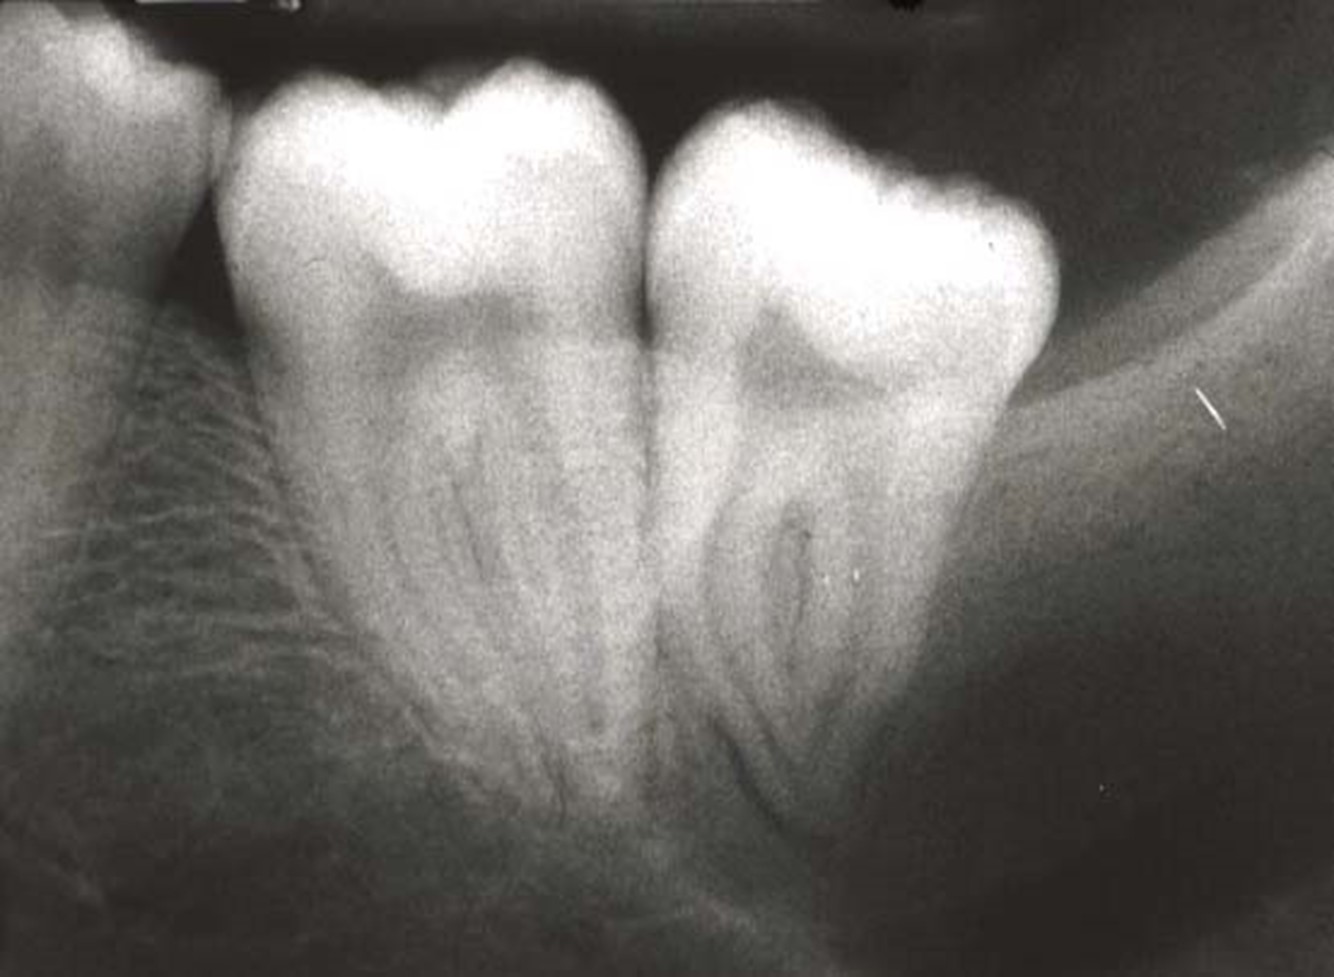

how to assess impaction

ne through 8 and 7, where 8 lies in relation to 7

26

impaction of 8s?

LR8 - mesially impacted LL8 - horizontally impacted

27

LR8 - horizontally impacted LL8 - distoangular impacted

28

hardest impaction to extract?

distally impacted 8s need to remove distal bone

29

LR8 - true vertical impaction LL8 - distal impaction